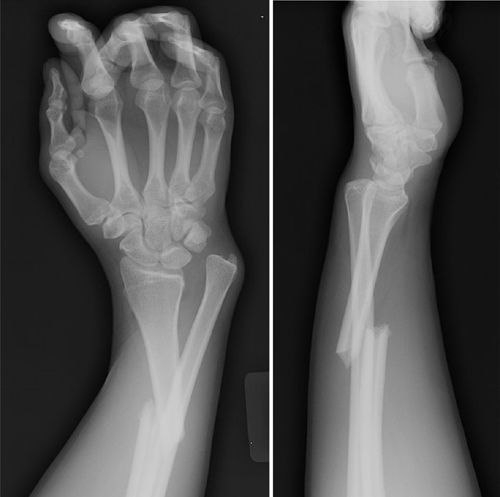

Galeazzi Fracture is defined as a fracture of the distal or middle third of the radius accompanied by dislocation or subluxation of the distal radioulnar joint. It is often referred to as a “fracture of necessity” because surgical management is usually required in adults.

image